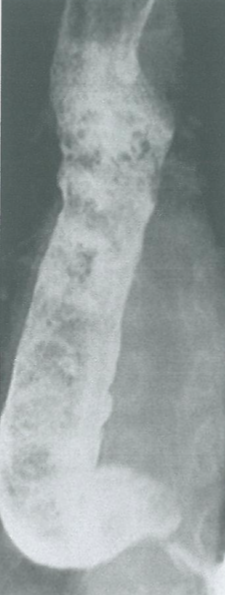

Varice esofagiene